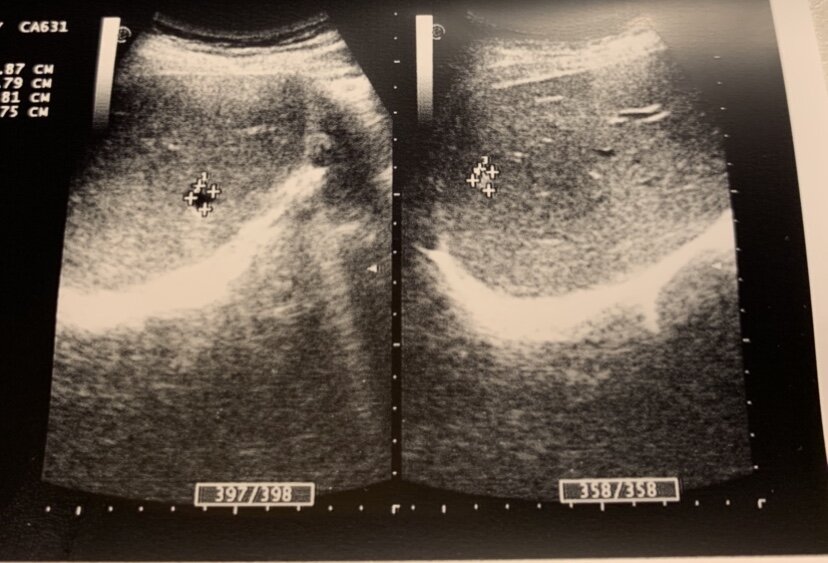

Слева на Узи- киста печени, справа- признаки гемангиомы

При проведении УЗИ пациентке я обнаружила три гиперэхогенных образования в правой доле печени, с четким ровным контуром, однородной структуры. Такая картина характерна для доброкачественных гемангиом.

Гемангиома - это доброкачественная сосудистая опухоль.